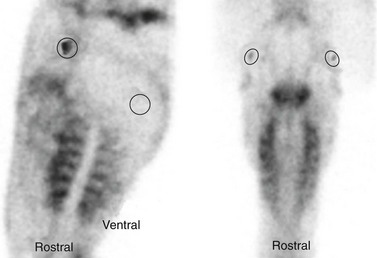

Identifying arthritis of the TMJ radiographically is often difficult, and other methods of imaging the joint, such as ultrasonography or scintigraphy, may be more useful. Ultrasonographic features of an arthritic TMJ include an irregular contour to both the temporal and mandibular components of the joint and an abnormally large volume of synovial fluid (Fig. 23.3). Typical scintigraphic findings include a mild to moderate increase in radiopharmaceutical uptake over the affected joint compared to the unaffected, contralateral TMJ. Arthrocentesis of the arthritic TMJ yields synovial fluid that is less viscous than normal and that has a normal nucleated cell count and a normal or mildly elevated concentration of protein. Proliferative new bone formation and cartilage loss are features observed during arthroscopic examination of the joint (Fig. 23.4).

Scintigraphy is an imaging modality that portrays function rather than morphological changes. It is the most sensitive of all imaging modalities for a variety of diseases, including dental disorders.27 To examine the TMJs of a horse scintigraphically, the horse is injected intravenously with 5 MBq/kg 99mTc-phosphonate. This dosage equates to half the dose usually used for imaging other parts of the horse, but in our experience, this reduced dose is sufficient to evaluate the head. We have found that the vascular and soft tissue phases are not useful for this area, and therefore we perform only a bone phase, usually about three hours after injection. Left and right lateral projections and a dorsal projection, each centered over the TMJ of interest, are acquired. Both TMJs should be adjacent to the camera during acquisition of images to avoid differences in radiopharmaceutical uptake caused by distance attenuation of the gamma radiation.

The resulting images should be evaluated visually, as well as quantitatively, by defining regions of interest (ROI) over the TMJs. On the dorsal projection the ROIs are compared directly, whereas on the lateral projections reference ROIs are defined over the ramus of the mandible (Fig. 23.7). The ratio between the ROI over the TMJ and the reference ROI is calculated and compared between sides. Radiopharmaceutical uptake by structures of the head, including the TMJs, varies with the age of the horse. The TMJs of young horses take up considerably more of the radiopharmaceutical drug than does the relatively inactive rest of the mandible, whereas the TMJs of old horses often cannot be differentiated from the surrounding tissues (Fig. 23.8). In our experience, a difference in radiopharmaceutical uptake by a TMJ of more than 25 % is indicative of disease of that joint.

Fig. 23.7 Lateral (left image) and dorsal (right image) scintigrams of the TMJs of a horse, 3 hours after the horse was injected with TC99m-methylendiphosphonate. Regions of interest are drawn around the TMJs, and reference regions of interest (ROIs) are defined over the ramus of the mandible. The ratio between the ROI over the TMJ and the reference ROI is calculated and compared between sides.